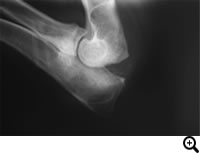

診断

レントゲン検査、関節鏡検査

治療

分離した肘突起の肘頭への固定、分離した肘突起の切除